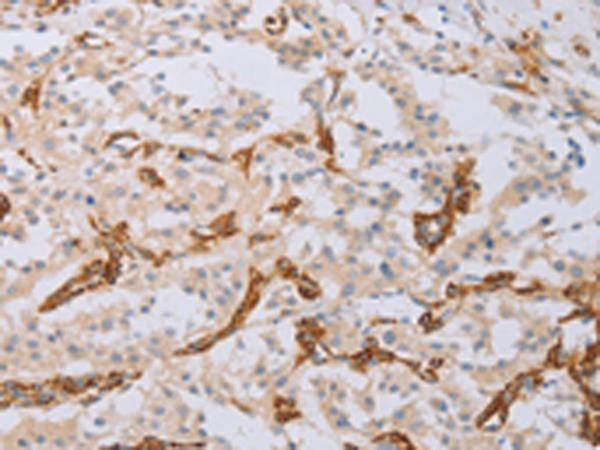

分类: 科研抗体货号: P07472别名: LC17; ESMLC; LC17A; LC17B; MLC-3; MLC1SM; MLC3NM; MLC3SM; LC17-GI; LC17-NM应用: WB,IHC反应种属: Human, Mouse, Rat